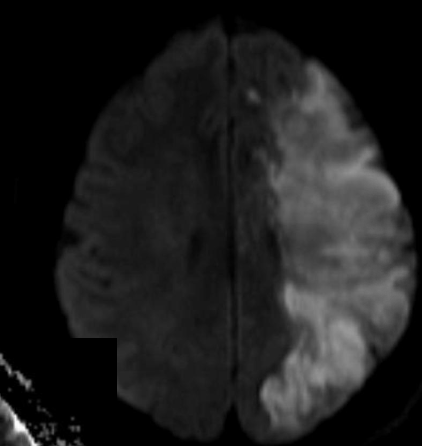

EVC isquémico

RM DWI